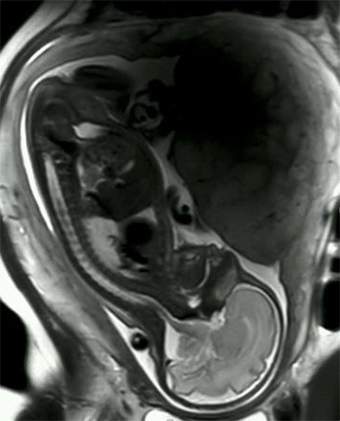

Pregnany scan on the wide bore scanner

The laboratory is equipped with the latest 3 Tesla (3T) Philips Ingenia Wide Bore MRI system having an open bore diameter of 70 cm giving greater level of patient comfort.